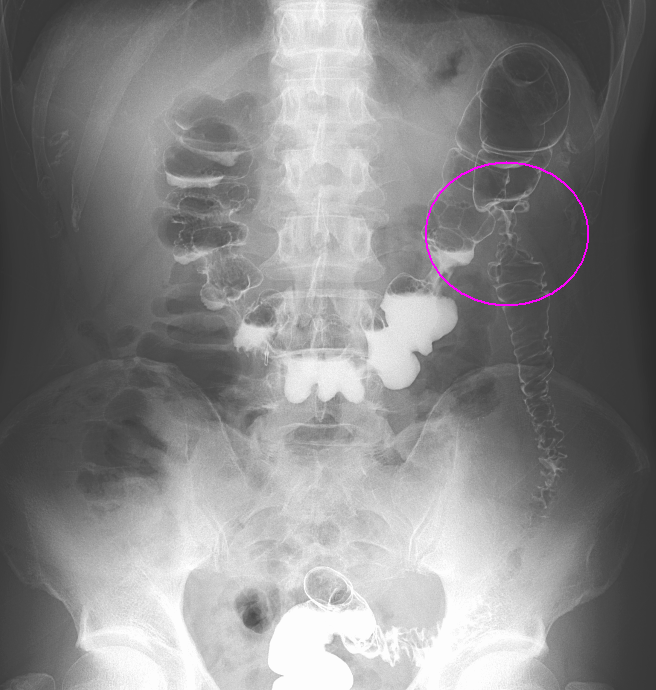

閉塞性大腸がんに対する大腸ステント治療

大腸がんが進行し腸が詰まってしまう閉塞性大腸がん(大腸がん腸閉塞)に対する治療です。従来は人工肛門を造設して対処していましたが、人工肛門はケアの負担やにおいに対する不安などからQOL(生活の質)低下が避けられません。そのため当院ではステントと言われるメッシュ構造の金属製の網を用いて詰まりを解消し、人工肛門を回避する治療を行っています。大腸ステント治療は緩和治療を目的に行う場合と根治手術前に全身状態の回復を目的として行う場合があります。

ステント留置後(内視鏡画像)

ステント留置後(レントゲン画像)